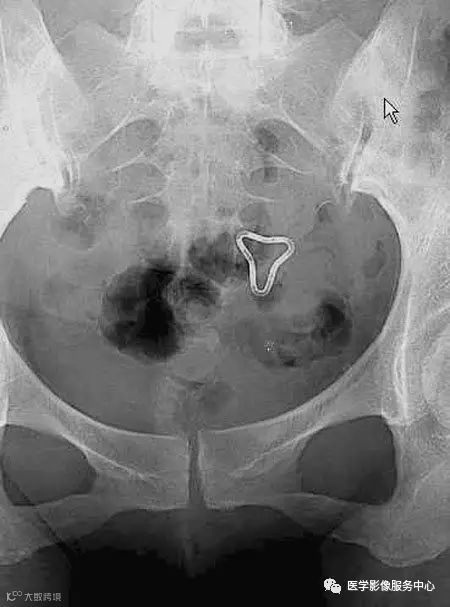

病人女性,外伤后骶尾部疼痛,dr片示骶尾关节对应关系差,骶5椎体欠规则。ct重建示骶5椎体粉碎性骨折!

X线